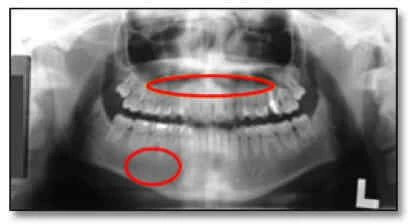

Mật độ lý tưởng phải đảm bảo cho các cấu trúc không bị che khuất bởi các vùng tối, các vùng “cháy sáng” hoặc các vùng quá sáng (các vùng “trắng xóa” hiển thị trên phim).

Bằng mắt thường có thể đánh giá điều này bằng cách nhìn vào vùng hàm dưới và vùng liên quan đến các chóp của răng ở hàm trên. Ở hàm trên, điều này thể hiện rõ nhất khi lưỡi không được giữ ở vị trí chính xác trong quá trình tiếp xúc toàn cảnh.

Mật độ quá nhiều hoặc không đủ có thể dẫn đến những sai sót trong quá trình chuẩn đoán như không phát hiện được các đặc điểm của răng, thậm chí là bệnh lý. Hình ảnh tối hoặc mật độ cao thường là do đánh giá quá cao kích thước tổng thể, tầm vóc và mật độ xương của bệnh nhân trong khi hình ảnh nhạt hoặc mật độ thấp thường do đánh giá thấp kích thước tổng thể, tầm vóc và mật độ xương của bệnh nhân.